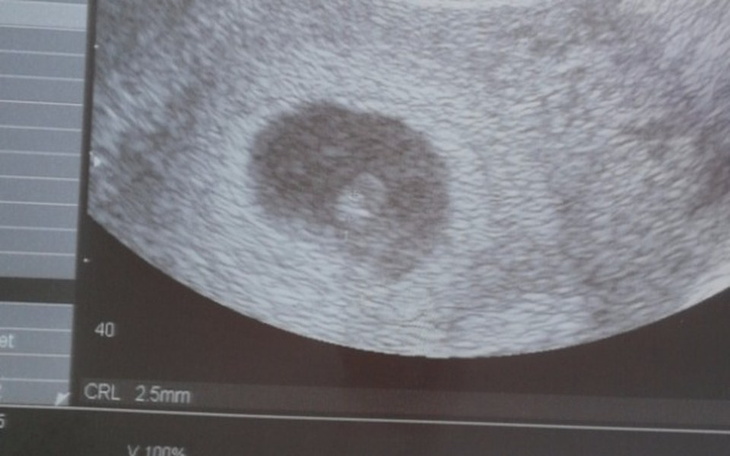

Cześć wszystkim mam 24 lata czekam na nasze małe szczęście. Z narzeczonym ucieszyliśmy się ogromnie gdy tylko sie dowiedzieliśmy. Po kilku tygodniach euforii przyszło realne myślenie co dalej. Najmowane mieszkanie robota na najniższa krajowa sporo długów. Czemu o tym mowie? Wcześniej o tym nie myśleliśmy, bardzo sie kochamy nie wiele nam potrzeba zawsze sobie radziliśmy ale teraz jak bedzie dziecko? Chcemy zacząć z nową karta bez długów aby w 100% poświęcić się dziecku. Wzięliśmy kredyt na samochód który nadal spłacamy a taki stary złomek ale jezdzi, sprzedac go nie możemy bo jest bardzo potrzeby. Narzeczony juz zmienia prace na lepszą a ja niestety musze juz siedzieć w domu :( Bardzo prosze o jakąkolwiek pomoc na nasz start. Długów ogólnie mamy 20000zl wpisałam połowę kwoty na druga połowę juz pracujemy ile mamy tylko sił.